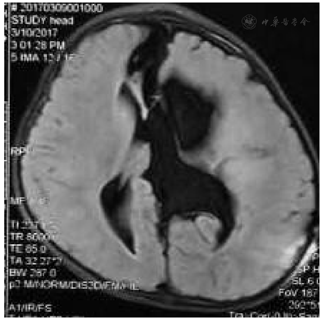

入院后行蛛网膜囊肿-腹腔(Cystoperitoneal,CP)分流术,初始开放压力设定为18 cmH2O,后每间隔3-6月调低2-3 cmH2O;术后2月MRI发现蛛网膜囊肿缩小;术后22月MRI发现囊肿进一步缩小,可见囊肿内分隔和透明隔,进一步行内镜下囊肿分隔和透明隔造瘘术,术后每2-3月逐步将分流阀压力从9 cmH2O调至15cmH2O;造瘘术后3月复查MRI发现囊肿进一步缩小、脑皮层增厚;

MRI检查示左侧额颞顶部巨大蛛网膜囊肿,脑组织严重受压,伴有脑积水,2014-12行蛛网膜囊肿腹腔分流术,初始开放压力设定为18 cmH2O,后每间隔3-6月调低2-3 cmH2O;术后2月MRI发现蛛网膜囊肿缩小;术后22月MRI发现囊肿进一步缩小,可见囊肿内分隔,入院进一步行内镜下囊肿分隔和透明隔造瘘术,术后逐步将分流阀压力9cmH2O调至15cmH2O;

造瘘术后三月复诊复查MRI发现囊肿进一步缩小、脑皮层增厚,左侧脑组织进一步复张,患儿右侧肢体活动较前明显好转、肌力V级。术后7年随访患儿已上一年级,家属诉患儿于学校学习、活动表现无明显异常。